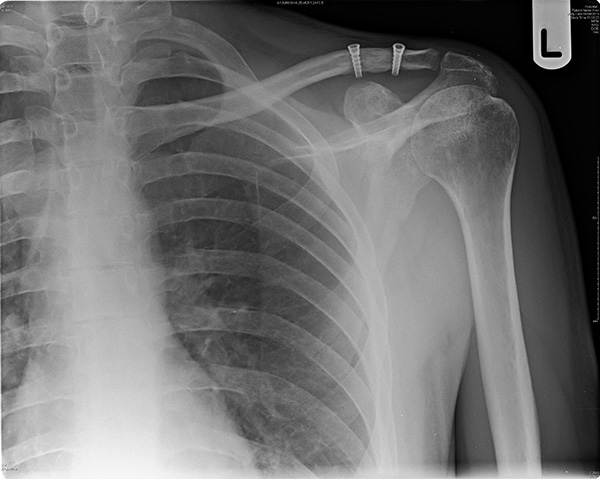

Рентген плеча: примеры снимков и их расшифровка

:background_color(FFFFFF):format(jpeg)/images/library/10853/IMG-0020-00001.jpg)